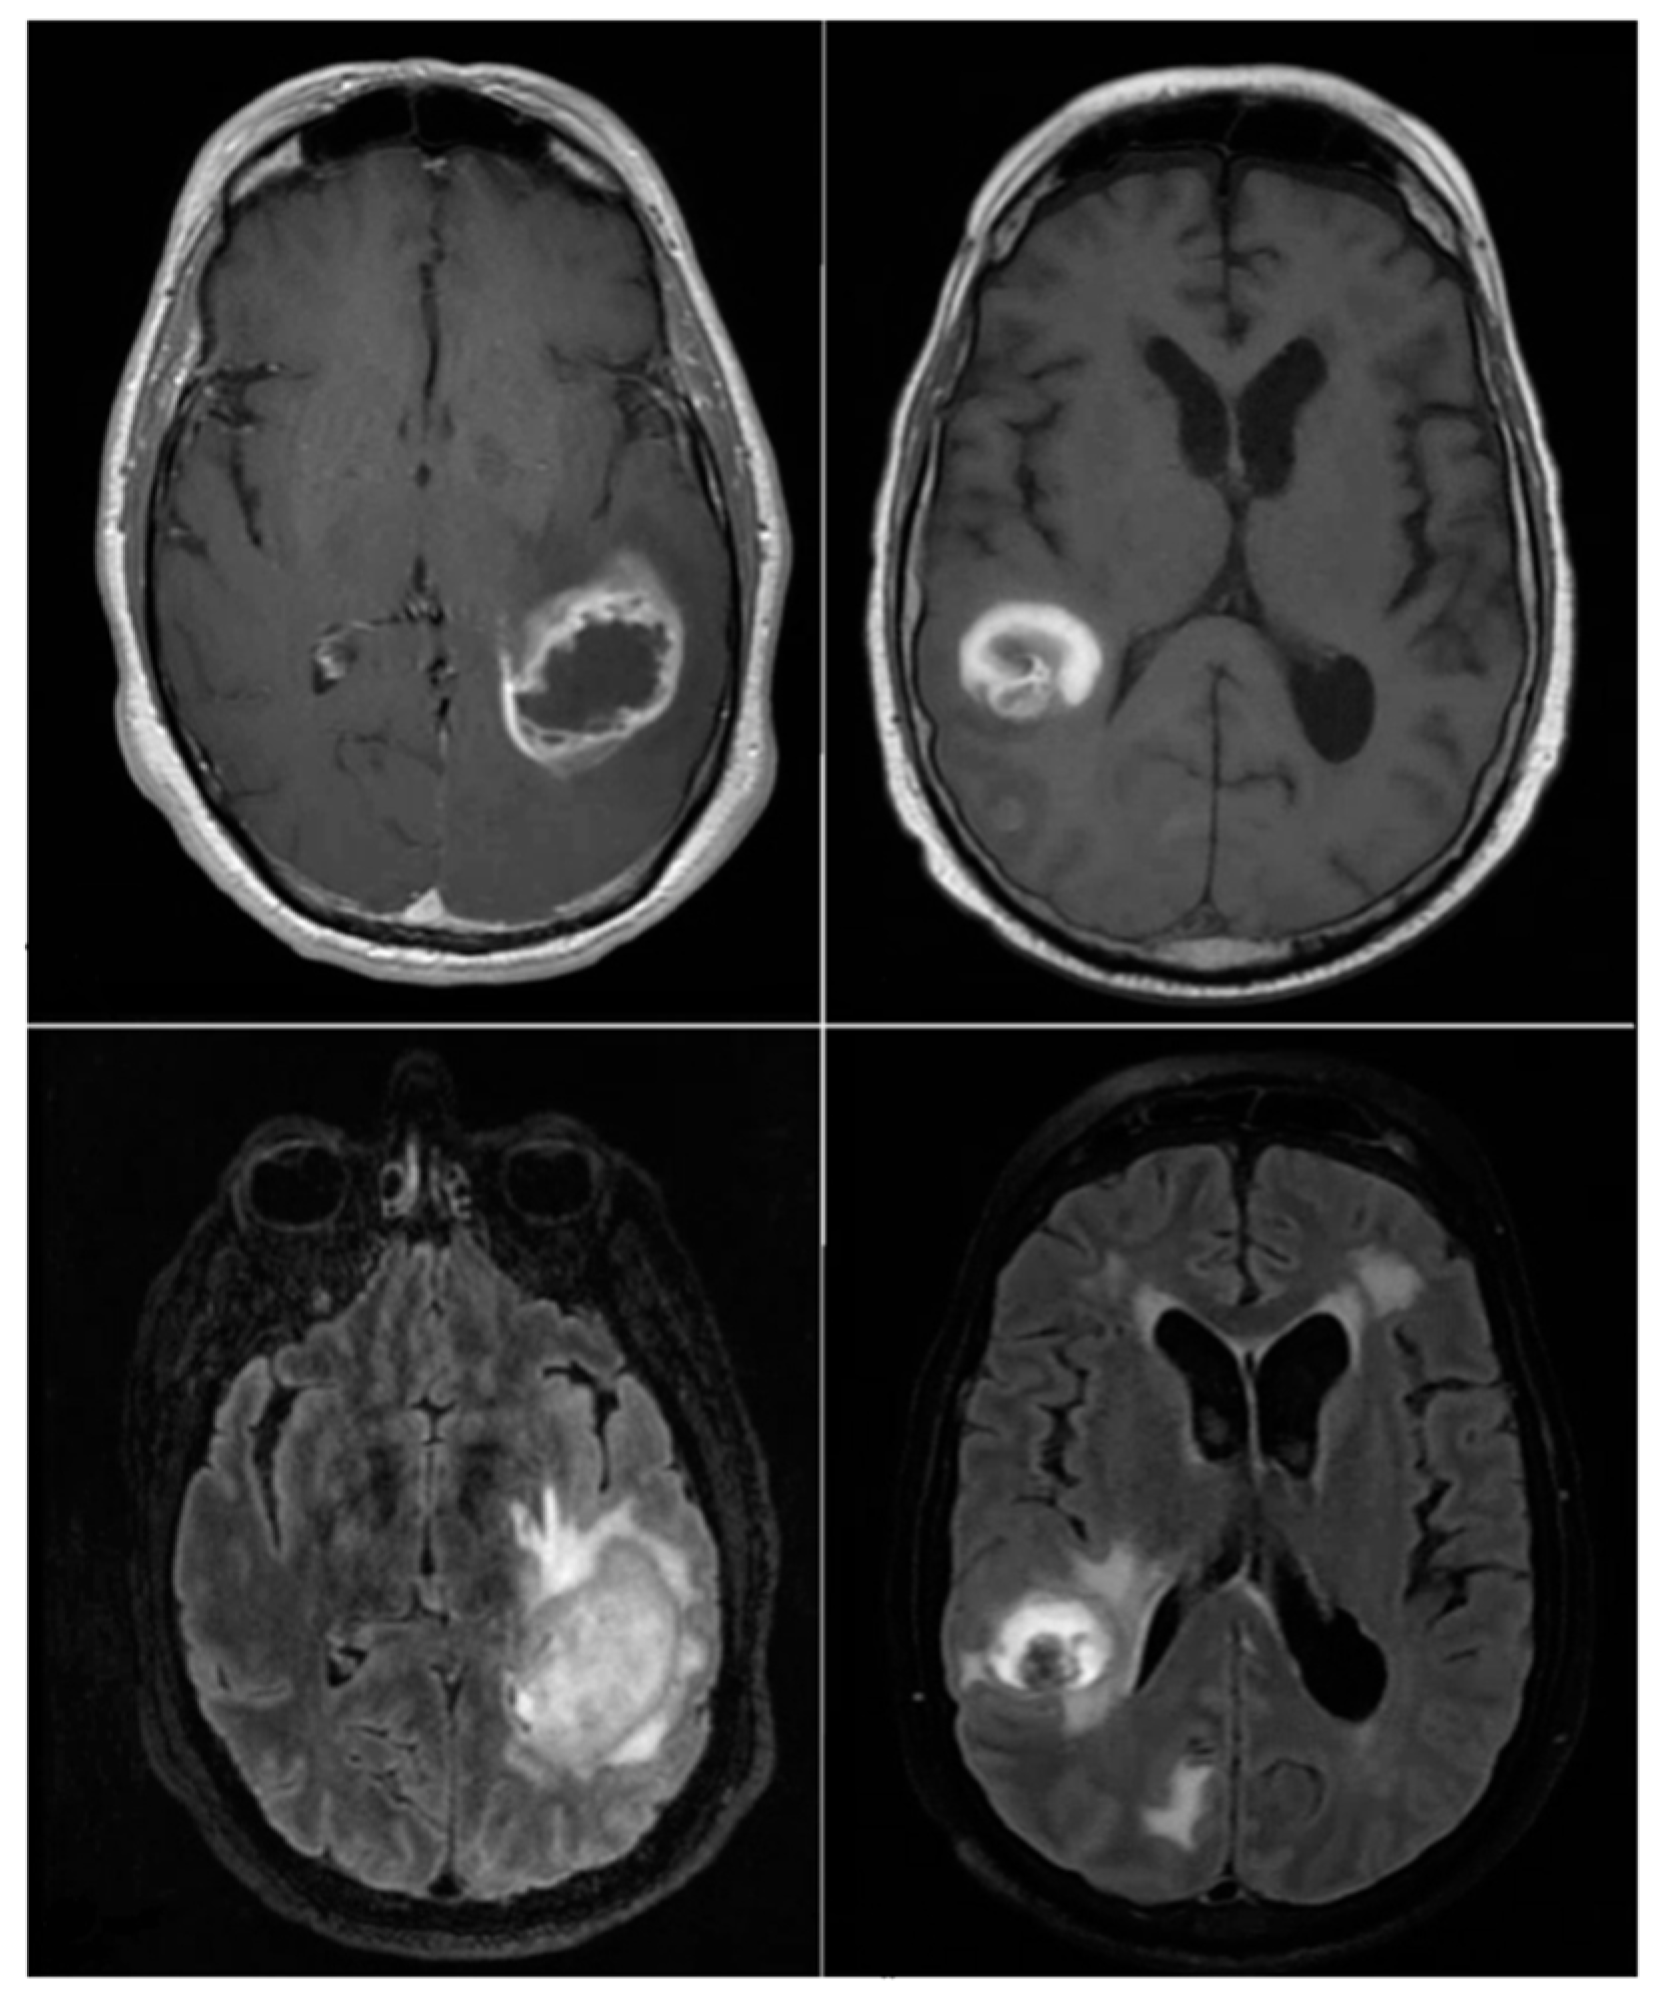

2.4. Image Dataset

The brain_met_1 image dataset was stored on the cloud (using Google Drive), consisting of two subfolders: progression and regression. For training, the train_ds was used and for validation, the valid_ds was used. The image dataset contains 3194 MRI brain metastasis images, with 2320 images of regression class ‘1’ and 874 images of progression class ‘0’. See example of images from the dataset in Figure 1.

Figure 1. Example of images from the dataset.

Tomography 11 00015 g001